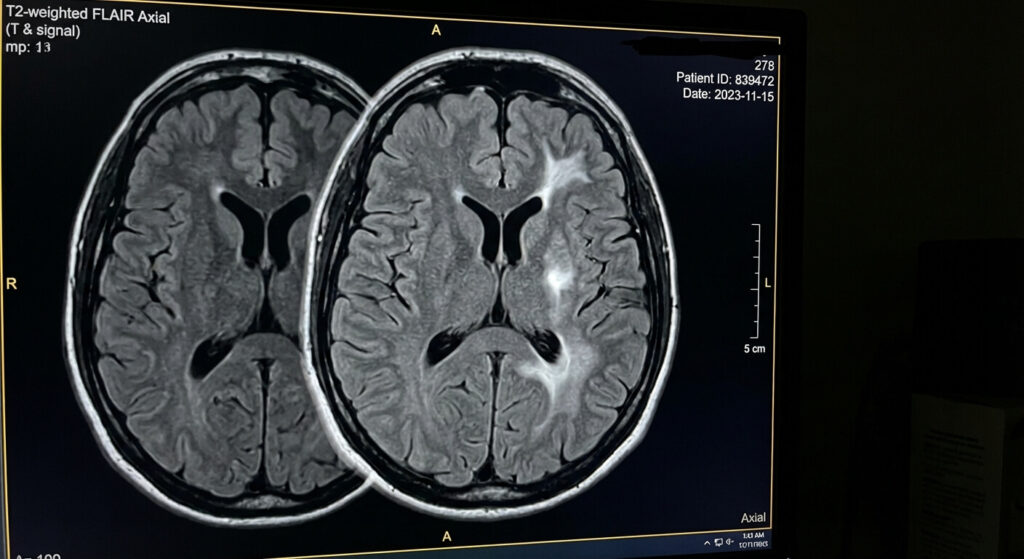

L’apparition de foyers inflammatoires sur les séquences T2 (et sa variante très utilisée, la séquence FLAIR, qui efface le liquide normal du cerveau pour ne laisser briller que la maladie) ouvre un éventail diagnostique très large.

💉 Pourquoi utilise-t-on la séquence FLAIR plutôt que le T2 simple ?

Le cerveau baigne naturellement dans un fluide appelé le Liquide Céphalo-Rachidien (LCR), qui remplit les ventricules. Sur une séquence T2 classique, ce LCR est d’un blanc éclatant. Si une lésion inflammatoire (aussi blanche) se trouve juste à côté du ventricule, elle devient invisible (ton sur ton). La séquence FLAIR (Fluid Attenuated Inversion Recovery) est une séquence T2 modifiée par ordinateur : elle « éteint » le blanc du liquide naturel pour le rendre noir. Ainsi, la moindre petite lésion pathologique gorgée d’eau brille intensément comme une étoile dans la nuit, la rendant inratable pour le radiologue.